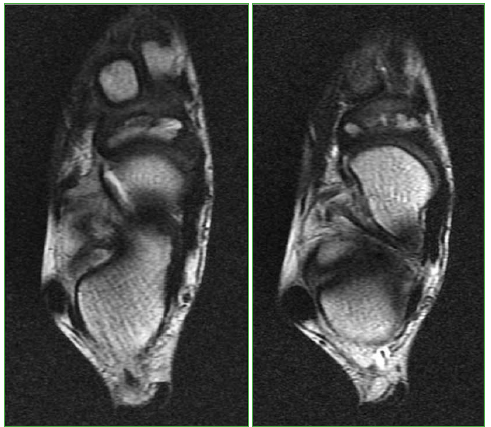

Instrucción Ortopédica de Posgrado - Imágenes. Resolución del caso.

Trueba, R. (2020). Instrucción Ortopédica de Posgrado - Imágenes. Resolución del caso. Revista De La Asociación Argentina De Ortopedia Y Traumatología, 85(2), 184-186. https://doi.org/10.15417/issn.1852-7434.2020.85.2.1076

Instrucción Ortopédica de Posgrado - Imágenes-Resolución

Ricardo Trueba, Departamento de Resonancia y Tomografía Computada, Grupo Médico Rostagno, Diagnóstico por Imágenes, Ciudad Autónoma de Buenos Aires, Argentina